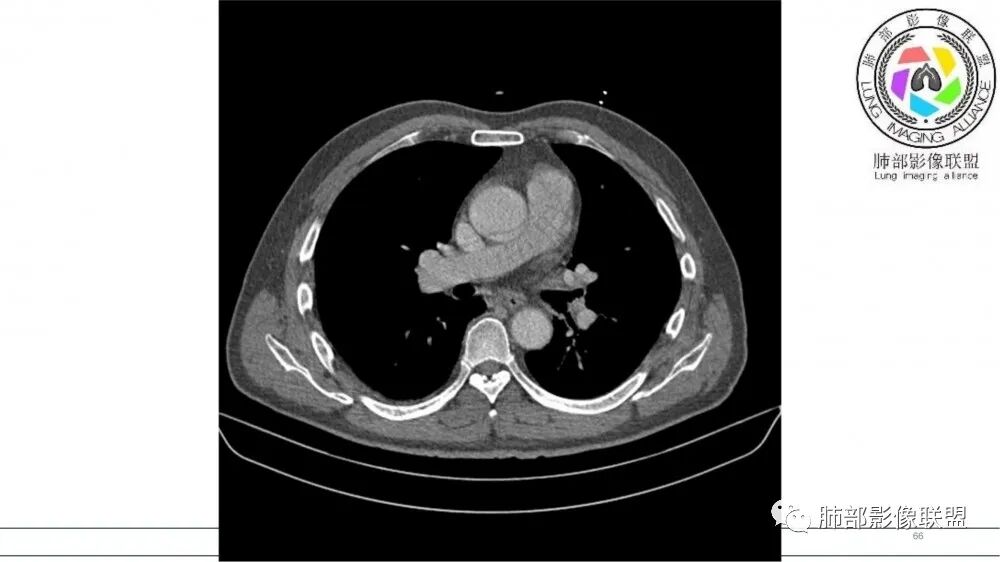

左肺上叶前段支气管内铸形生长软组织影,增强后均匀强化,远侧见斑片状磨玻璃影。考虑恶性病变,粘表?粘液腺?

老年男性,左肺上叶前段支气管内铸形阴影,增强后病灶不均匀强化,内部有坏死?远端可见斑片状阴影(阻塞性肺炎)。考虑恶性病变,老年人,鳞?类癌?粘表不能排除。

老年男性,肺气肿,吸烟史,左肺上支气管腔内铸型高密度影,呈指套状,远端多发树芽,增强不均匀强化,考虑鳞癌,鉴别小细胞癌

老年男性,吸烟史,左肺上叶支气管塑形生长肿块,整体边缘较圆钝,不均匀强化,血管走形,形态较纤细,病灶远端可见花草样改变,恶性,先考虑小细胞癌鉴别鳞癌

老年男性,长期吸烟史。左上肺前段沿支气管走形的指套样病变,增强可见病灶强化(排除结核、ABPA(也无气喘症状)),远端多发点状高密度影。考虑恶性肿瘤,鳞癌可能性大。

指套征,扩张支气管内软组织强化,远侧肺野阻塞性炎,纵隔、左肺门肿大淋巴结;老年男性,吸烟,考虑鳞癌,鉴别小

老年男性,术前检查肺气肿背景,左肺上叶结节,沿支气管蠕虫样生长,左肺门及纵隔淋巴结肿大,增强扫描不均匀强化,血管包绕,结合吸烟史,考虑小细胞肺癌。

2021年8月6日晨读病例结果:小细胞肺癌

指套征:是影像征象,胸部平片表现为手指状密度增高影,以肺门为中心呈放射状分布,CT显示扩张支气管内低密度黏液栓形成或实性病变,呈管状、树枝状或卵圆形密度增高影;支气管扩张伴近端梗阻时,扩张支气管内部黏液分泌物不能排出而形成。可以伴随远端空气潴留征、阻塞性炎症。

研究报道,中心型 SCLC 经 CT 扫描后通常支气管表现为鼠尾样狭窄,肺门或纵隔肿块明显,由于肿块沿管壁生长表现为顺延支气管形态的不规则形状。病灶相对特征性影像学表现比如鸭蹼状、腊肠状、葫芦状及葡萄状改变,可以出现血管包埋,很少有空洞、空泡,较少引发肺不张,阻塞性炎症成都较轻。与一般肺癌比较,恶性程度高,侵袭力强、病灶很小就容易远处转移!Herzberg 等[19]研究指出,20%以上 SCLC 倍增时间短,预后不良。